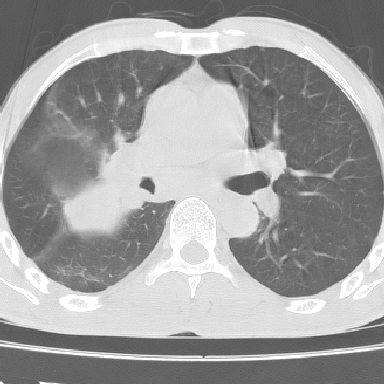

以下是引用lpc0ct在2006-11-28 16:12:00的发言:[br]大家图文并貌分析的太全面了,没有可说的,同意 [br] 右肺上叶中心型肺癌伴肺门、纵隔淋巴结转移.[br]

以下是引用dyqct在2006-11-28 16:00:00的发言:[br]右肺上叶中心型肺癌伴肺门、纵隔淋巴结转移。[br][br]